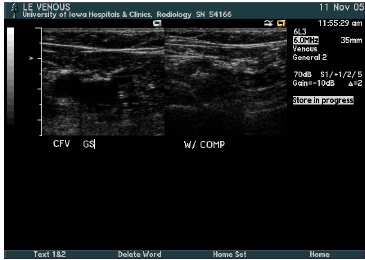

what is this?

trans CFV and GS junction *mickey mouse